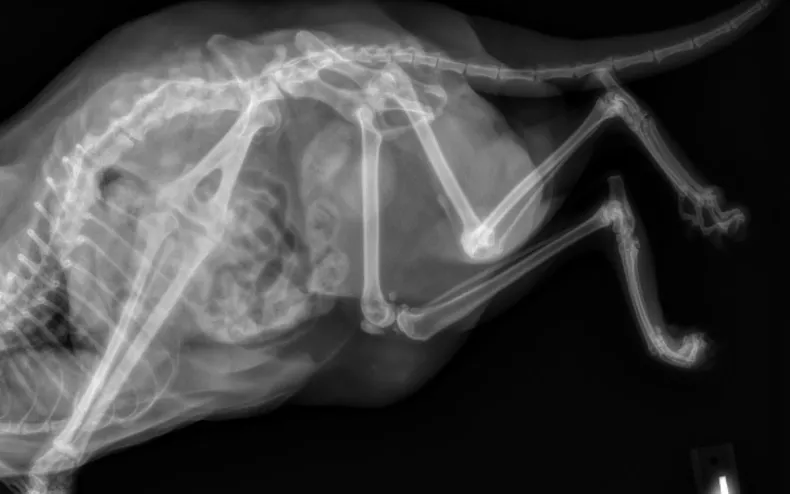

But one clear X-ray removed all doubt, this feline truly has an extra limb, and now her story is touching hearts around the world.

The reason? She has five legs, a rare condition that even vets can’t fully explain.

Her fifth leg is fully formed, fused at every joint, and sticks straight out in front of her back right leg.

It’s longer than her other legs, and she has no control over it.

Her recent X-ray confirmed the condition of her leg and helped doctors understand more about her situation.